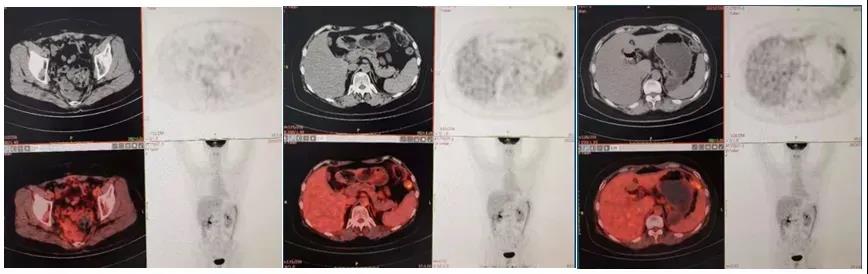

患者术后行基因检测,共检出BRCA基因3个明确致病性突变。2020年6月7日(化疗后20天)患者开始口服奥拉帕利300 mg bid维持治疗,出现恶心、呕吐及胃痛等严重的胃肠道反应,影响进食及生活,行止吐、补液等治疗,一段时间后症状稍改善。减少剂量服用仍有明显胃肠道反应,患者拒绝继续用药,停服奥拉帕利(奥拉帕利治疗历时1.5个月)。2020年7月24日开始改服尼拉帕利200 mg qd维持治疗。维持治疗期间,血CA125、HE4水平在正常范围内波动(图2),白细胞、血红蛋白、血小板正常范围内波动(图3)。2021年7月9日PET-CT未见肿瘤复发征象(图4)。2021年10月29日B超提示盆腔积液;脾、胰、未见明显占位病变;双侧颈内静脉、双侧锁骨下静脉、双侧股静脉、双侧腘静脉内未见明显栓子形成。

图4 2021年7月9日PET-CT情况